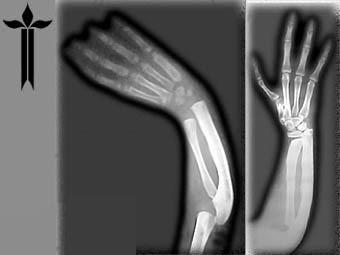

Рентгенография:

- Является основным и первым методом диагностики. Выполняется в двух проекциях (прямой и боковой), а иногда и в косых.

- Особенность рентгена при переломах зоны роста заключается в том, что хрящевая пластинка не видна на снимках, так как не задерживает рентгеновские лучи. Перелом определяется по смещению эпифиза, наличию метафизарного или эпифизарного фрагмента, расширению или неровности зоны роста.

- Часто для сравнения делают снимок здоровой конечности, особенно у маленьких детей, чтобы исключить естественные варианты строения или физиологические зоны роста, которые могут быть ошибочно приняты за перелом.

- Рентгенография позволяет определить тип перелома по классификации Солтера-Харриса (Salter-Harris).